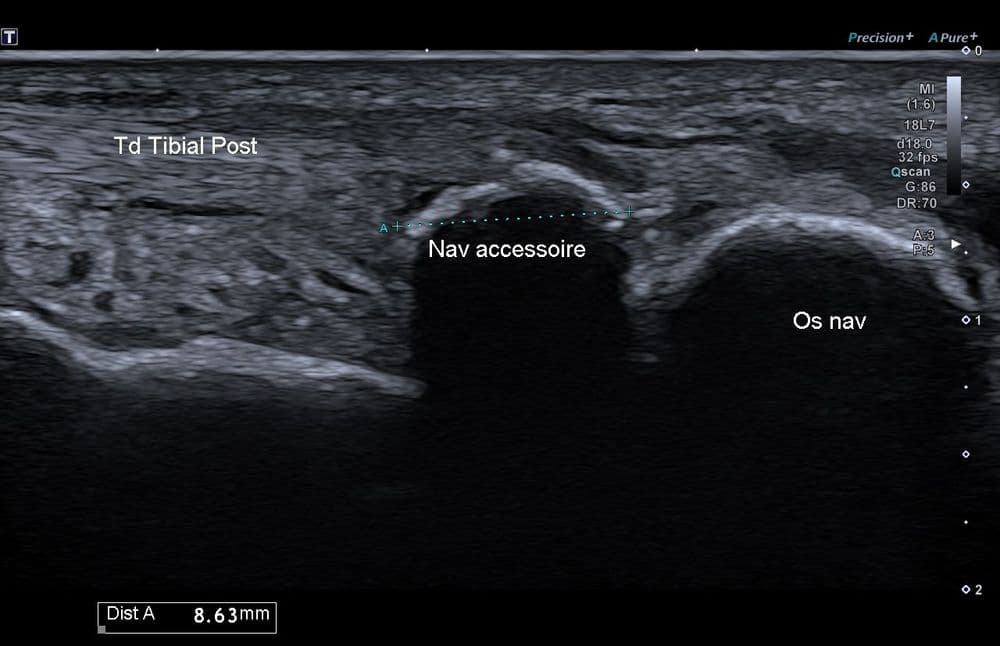

Enthésopathie du tendon tibial postérieur sur os naviculaire accessoire de type 2.

US